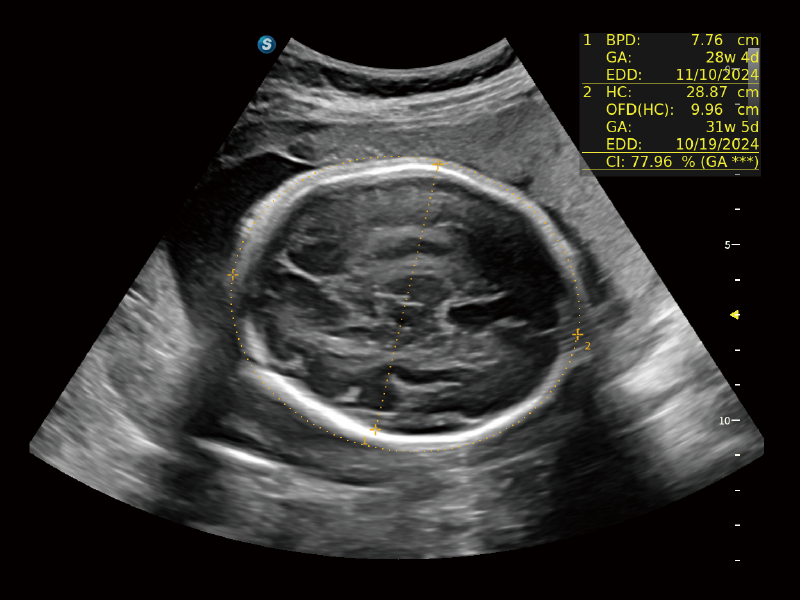

作為開立醫(yī)療全新打造的超高端旗艦超聲產(chǎn)品,從探頭抬起喚醒開啟掃查到多維探頭發(fā)射接收,通過先進(jìn)的場(chǎng)成像發(fā)射、自適應(yīng)聚合重建等技術(shù),基于RF Data原始射頻數(shù)據(jù)在圖像生成、高端功能等方面實(shí)現(xiàn)突破,為婦產(chǎn)科、兒科提供全方位臨床解決方案。

夢(mèng)溪?P80以“關(guān)愛女性”為基石,提供全方位的解決方案,量身定制以滿足女性的健康需求,涵蓋婦科、生殖健康檢查、產(chǎn)前篩查及產(chǎn)后康復(fù)等領(lǐng)域。